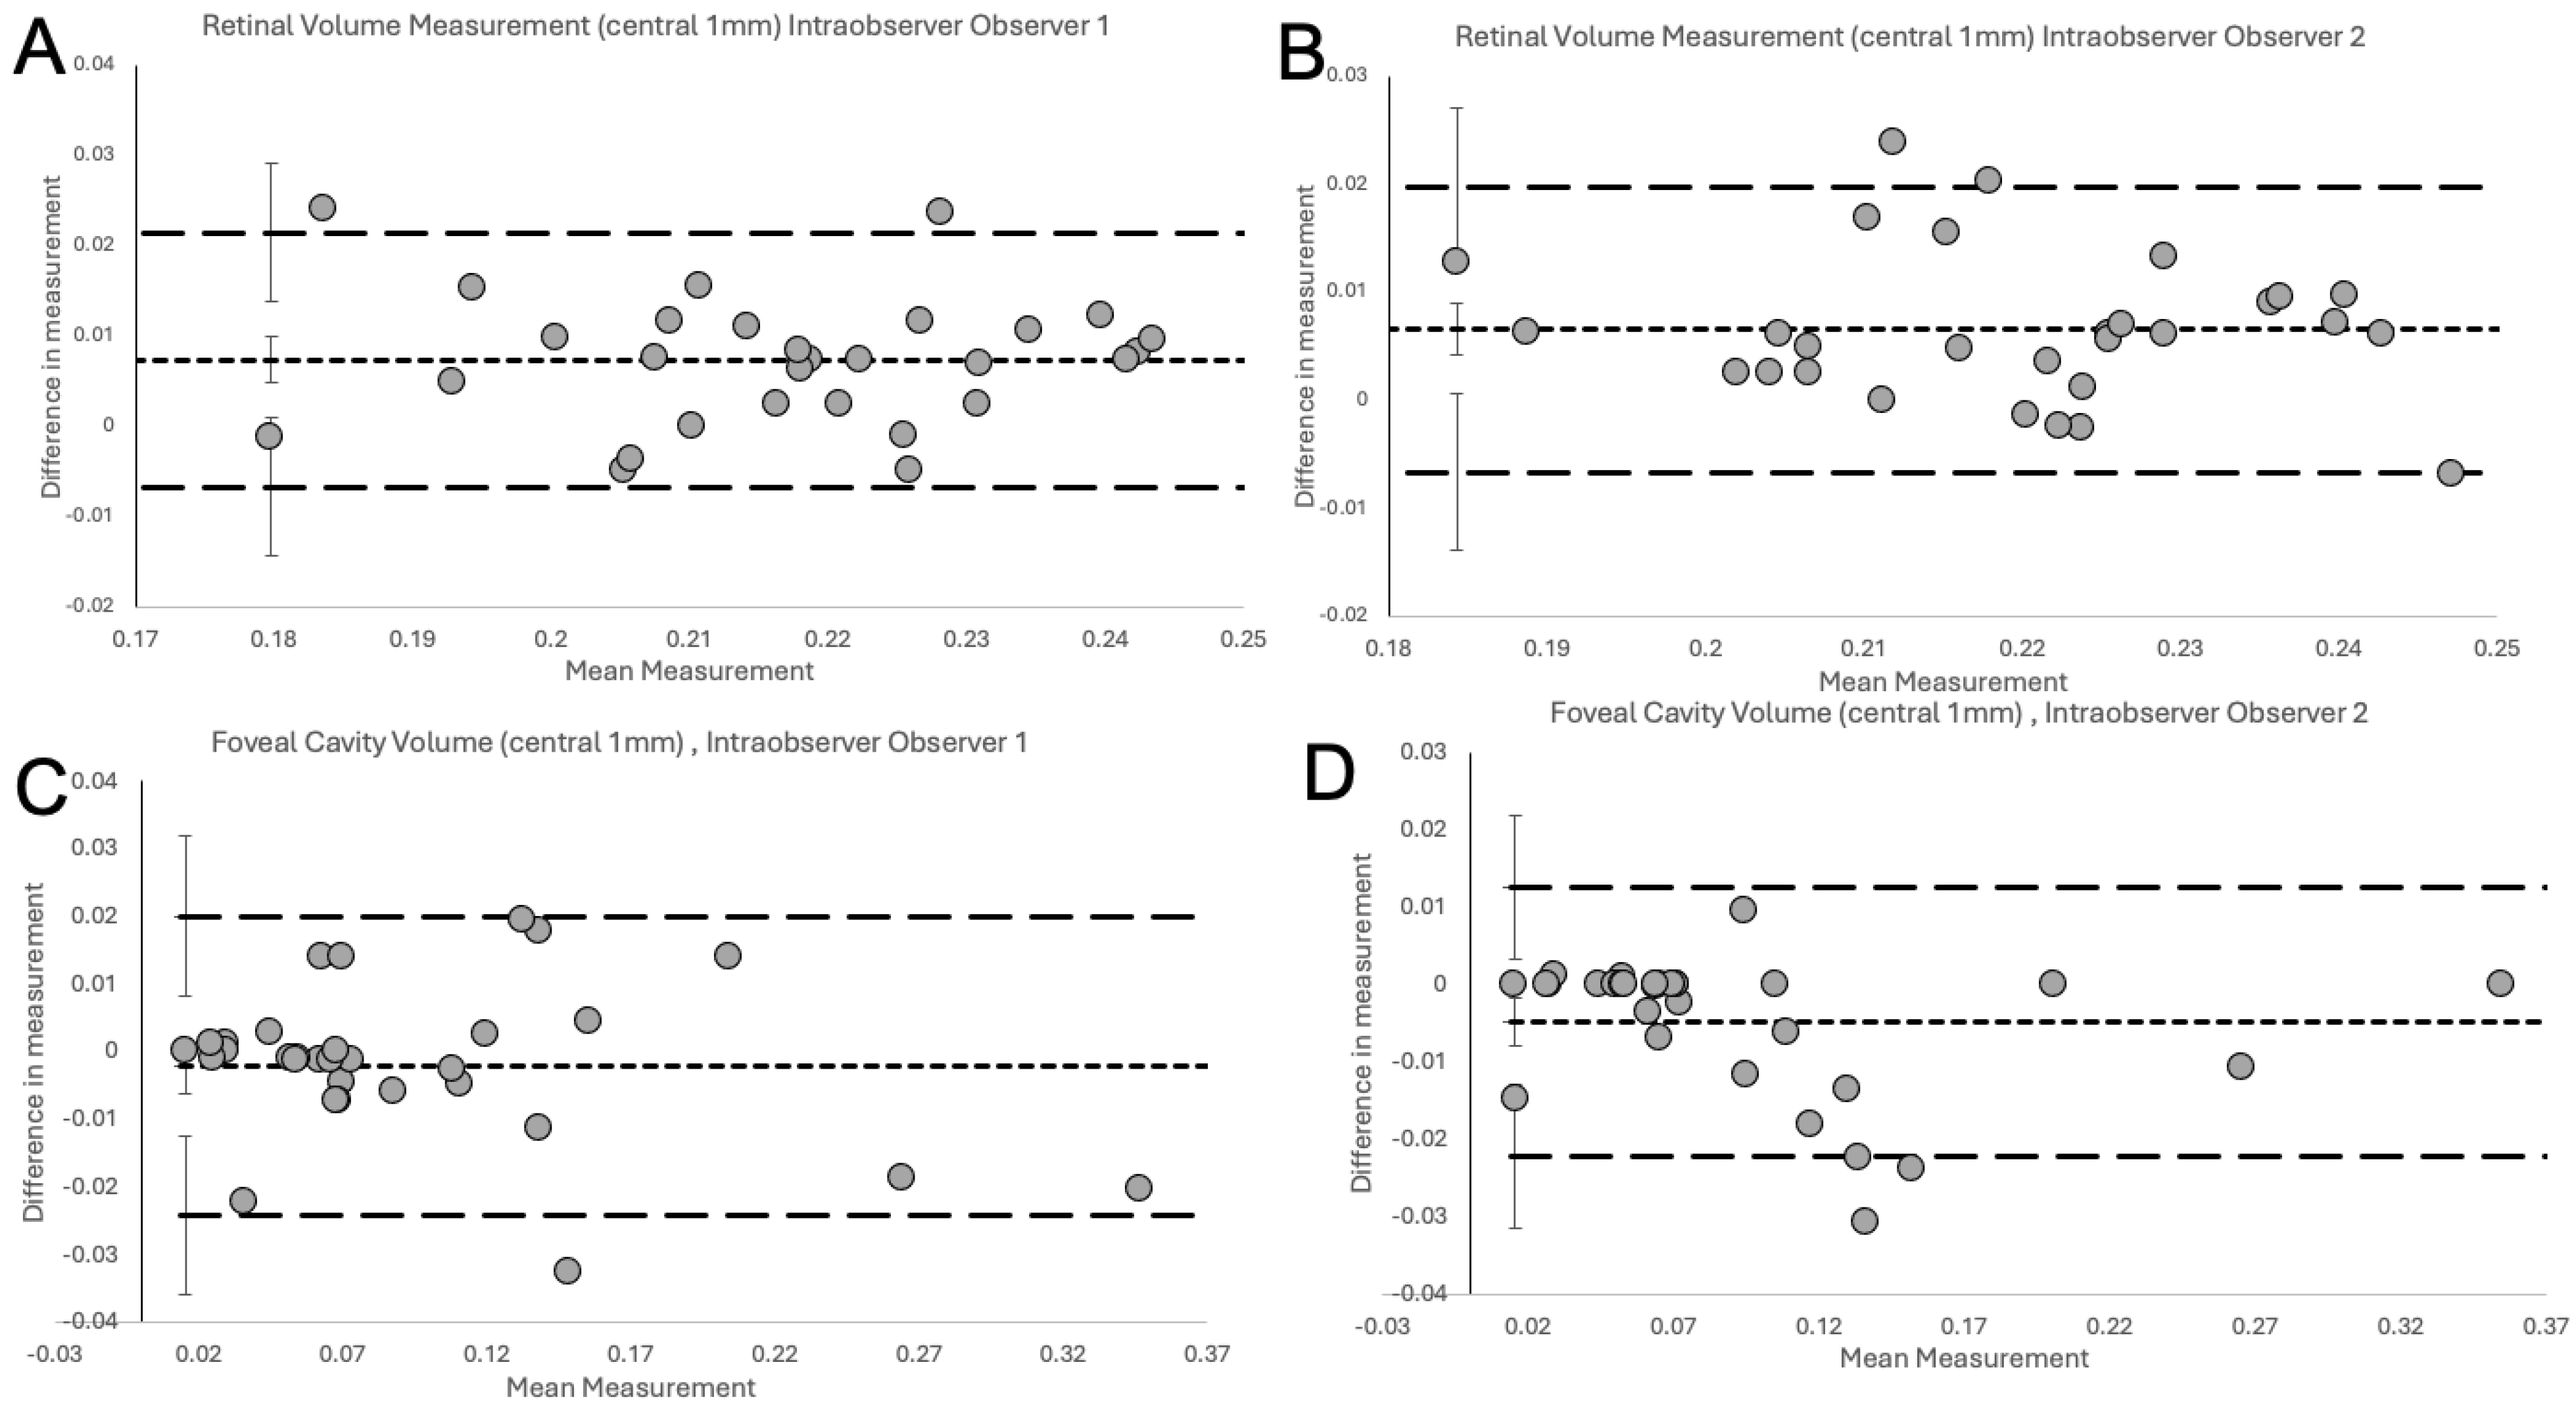

2.4. Statistical Analysis

3. Results

| Type of Comparison | n | Estimate of Bias (mm) | 95% CI (mm) | Lower Limit of Agreement (mm) | 95% CI (mm) | Upper Limit of Agreement (mm) | 95% CI (mm) | Coefficient of Repeatability (mm) |

|---|---|---|---|---|---|---|---|---|

| Intra-observer Total Retinal Volume | ||||||||

| Obs 1, Obs 1 | 30 | 0.0074 | 0.0048 to 0.0100 | −0.0067 | −0.0144 to 0.0010 | 0.0215 | 0.0138 to 0.0292 | 0.0141 |

| Obs 2, Obs 2 | 30 | 0.0066 | 0.0042 to 0.0090 | −0.0066 | −0.0139 to 0.0006 | 0.0198 | 0.0125 to 0.0270 | 0.0132 |

| Inter-observer Total Retinal Volume | ||||||||

| Intra-observer Foveal Cavity | ||||||||

| Obs 1, Obs 1 | 32 | −0.0021 | −0.0061 to 0.0020 | −0.0242 | −0.0359 to −0.0125 | 0.0201 | 0.0083 to 0.0318 | 0.0221 |

| Obs 2, Obs 2 | 32 | −0.0048 | −0.0080 to −0.0016 | −0.0222 | −0.0315 to −0.0130 | 0.0126 | 0.0034 to 0.0219 | 0.0174 |